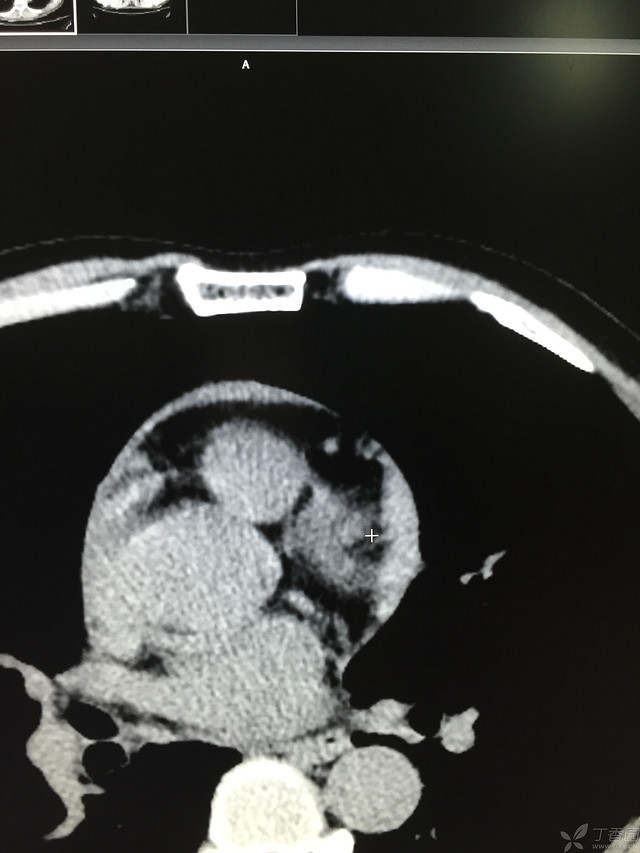

患者性别:男

患者年龄:64岁

简要病史:三天前休息时突发胸前区疼痛伴大汗,到当地医院输液治疗后缓解,3小时前情绪激动后再次出现胸痛伴大汗,胸部压迫感,持续不缓解入院,到当地医院测血压180/?mmHg泵入硝酸甘油转入我院。

体格检查:血压94/72mmHg(右侧)96/74mmHg(左侧),心率78此/分,其他未见阳性体征